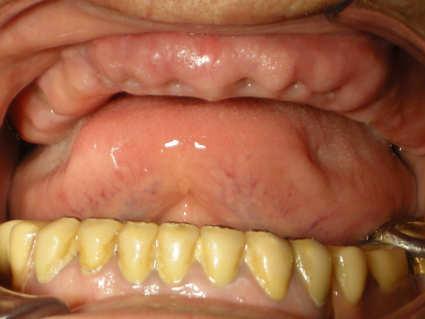

Implantology

Dr. Valter Pirazzoli